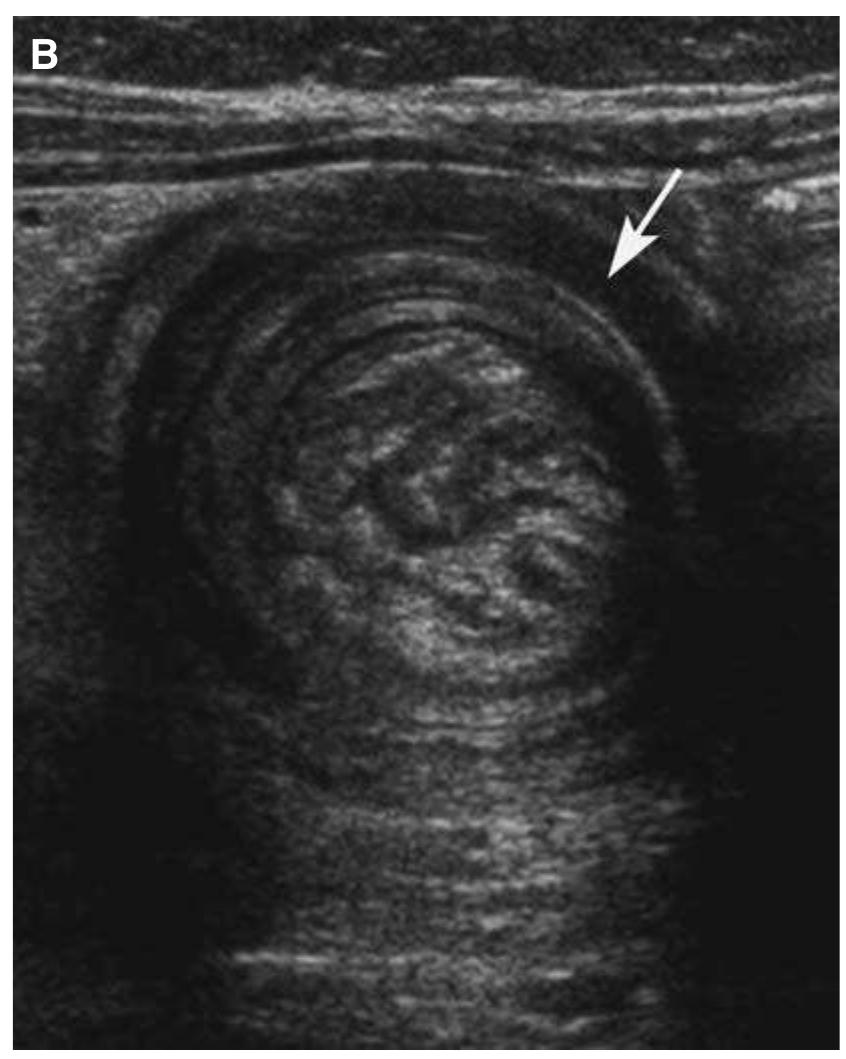

The knee is an anatomically and biomechanically complex joint. Few studies have been published reporting the type and frequency of knee injuries. However, this information that may help to prevent, diagnose, and treat knee joint injuries.... more